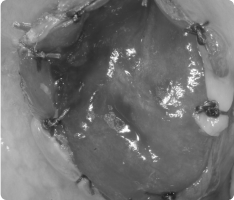

- 국소마취 하에 잇몸을 살짝 열고 숨어 있는 과잉치만 조심스럽게 제거합니다.

- 이후 잇몸을 봉합해 안전하게 회복되도록 합니다.

수술은 짧은 시간에 안전하게 진행되며, 대부분 아이들은 수술 후 큰 불편 없이 회복합니다.